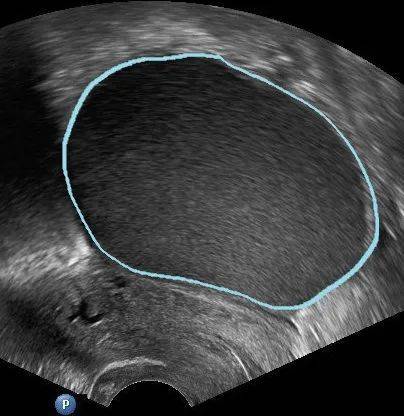

“戏精”卵巢囊肿的种类繁多,在妇科超声下它实际是一种卵巢内部或表面形成的囊状结构,统称为“卵巢囊肿” ,但这种影像上的改变并非一定与肿瘤相关,并不能马上称之为一种“疾病”,其实质“千变万化”。

正如上文所说,由于B超下发现的毕竟只是一个影像,所以很多时候并不能判断囊肿的性质,还需要进一步随访 或检查才能判断。国际卵巢肿瘤分析组织(IOTA)将卵巢肿瘤的超声描述方法标准化,在以下识别卵巢肿瘤良恶性 的10个简单特征中,若卵巢肿瘤含有至少一个恶性肿瘤特征(M特征)而没有良性肿瘤特征(B 特征),则卵巢肿 瘤被分类为恶性肿瘤。